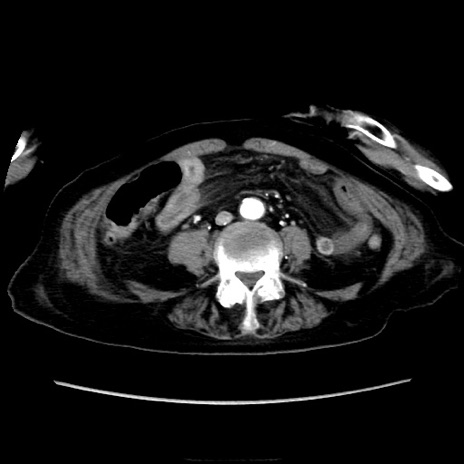

症例40(横断像)

【症例】90歳代女性

【主訴】腹痛・嘔吐

【現病歴】 食欲低下、嘔吐があり昨日他院受診。肺炎と診断され入院となる。入院後より腹部全体に圧痛あり。胃管留置され経過みていたが、症状持続するため、

当院転院となる。

【既往歴】胸椎圧迫骨折、胆石症

【身体所見】腹部:中央に激痛あり、圧痛あり、反跳痛不明

【データ】WBC 17100、CRP 18.82

他院CT

横断像